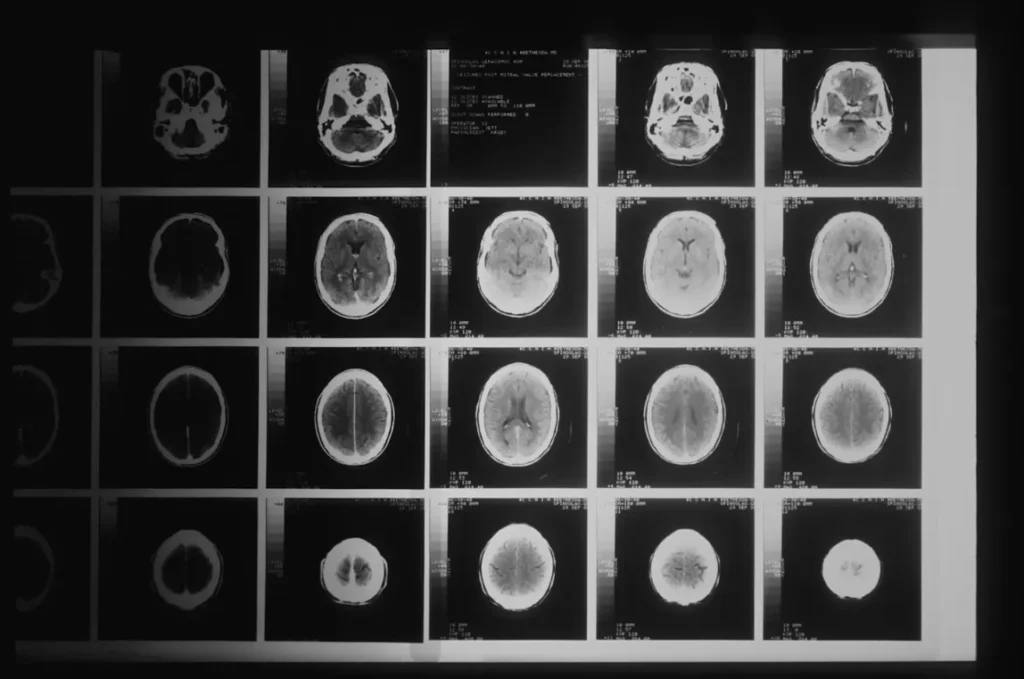

- Evaluación inicial: consulta, resonancia, TAC, análisis.

- Planificación quirúrgica: uso de neuronavegación y simulaciones 3D.

- Cirugía: bajo anestesia general, con monitorización continua.